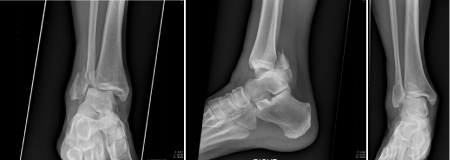

Figure 4 AP, Mortise & Lateral of Right ankle at 6 months post-operatively, 3 months s/p syndesmotic screw removal.

The patient was seen two weeks post-operatively. His incisions were well healed and his staples were removed at that time. The patient was then placed in a walker boot and remained non-weight bearing on the right lower extremity. He was seen back at six weeks for a range of motion check and subsequently scheduled for syndesmotic screw removal at 12 weeks from the initial surgery. The syndesmotic screw was removed three months from the original surgery the patient was allowed to place full weight on the right lower extremity with crutches and advance as tolerated. The patient was involved in physical therapy for strengthening after the removal of the syndesmotic screw which was successful. The patient was most recently seen at five months post-operatively and found to have full range of motion in the right ankle and no pain.